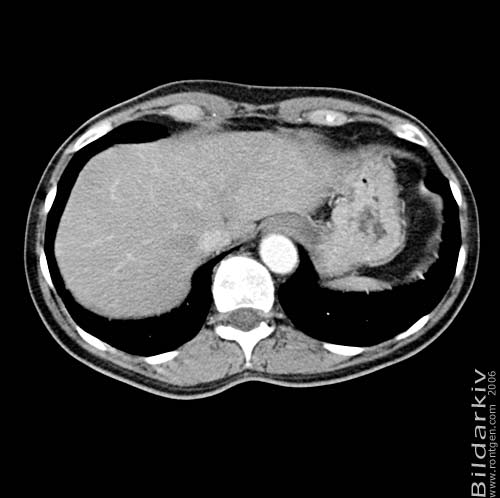

Thorax 50

Snitt över thorax med kontrast. Sk. mediastinum-fönstersättning.

CT Röntgen Helsingborgs lasarett

Mediastinum